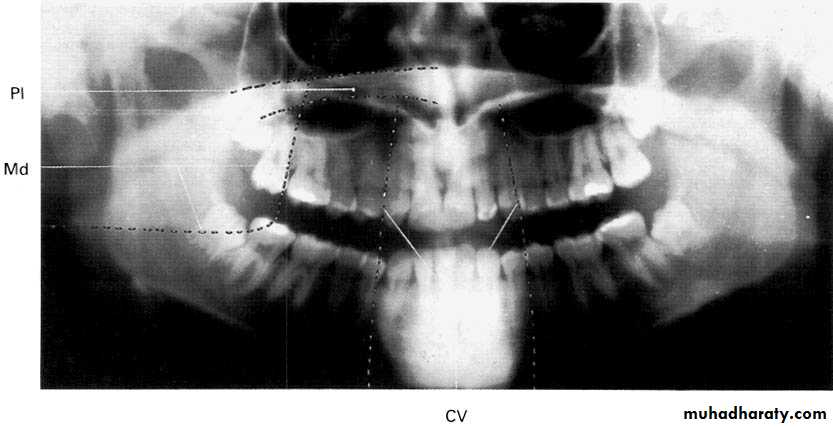

A dental panoramic tomograph showing the main anatomical ghost or artefactual shadows drawn in on one side of the radiograph, PI — palate, Md — mandible, CV — cervical vertebrae.